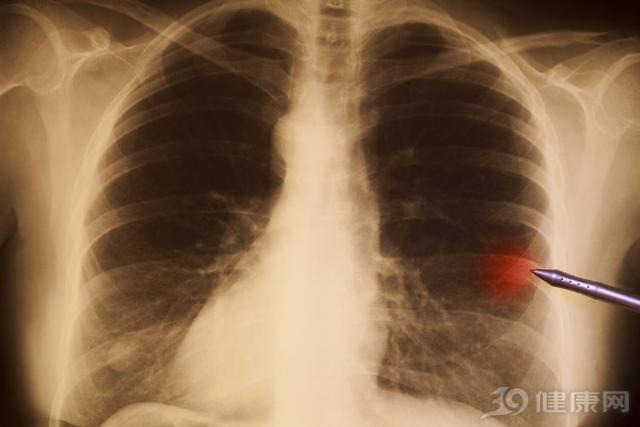

怎么判断肺结节是良性还是恶性

如果检查中肺结节有如下变化者,多考虑为良性:

1、短期内病灶外部特征变化明显,无分叶或出现极深度分叶,边缘变光整或模糊;密度均匀或变淡、在密度未增加的情况下病灶缩小或消失

2、病灶迅速变大,15天内增大1倍以上

3、实性结节2年以上仍稳定,但这一特征并不适用于磨玻璃样结节,因原位腺癌和微浸润腺癌阶段的磨玻璃结节可长期稳定。

肺结节在随访中有以下变化时,多考虑为恶性:

1、直径增大,倍增时间符合肿瘤生长规律;

2、病灶稳定或增大,并出现实性成分;

3、病灶缩小,但出现实性成分或其中实性成分增加;

4、血管生成符合恶性肺结节规律;

5、出现分叶、毛刺和或胸膜凹陷征。